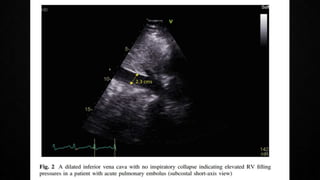

• Manifestations of RV pressure overload and dysfunction

• RV dilatation seen in >25% of patients with PE on TTE and is useful for risk stratification

of the disease

• 60/60 Sign : combination of a pulmonary ejection acceleration time (measured in the RV

outflow tract) of <60ms AND a peak systolic tricuspid valve gradient of <60mmHg

• McConnell’s sign : depressed contractility of the RV free wall when compared to the RV

apex

• Finding present only in 12-20% of unselected PE patients

• Decreased tricuspid annular systolic plane excursion (TAPSE) may also be seen in PE

• Mobile right heart thrombi (in up to 18% of PE in the ICU) essentially confirm the

diagnosis of PE and associated with high mortality rates

• Echo is not mandatory as a part of workup in hemodynamically stable patients with PE

• BUT in suspected high-risk PE, absence of echocardiographic signs of RV overload

practically excludes PE as the cause of hemodynamic instability. Can give a pointer

towards the differential diagnosis of the actual cause of shock

• Conversely, in a hemodynamically compromised patient with suspected PE, unequivocal

signs of RV pressure overload such as the McConnell’s sign or the 60/60 sign justify

emergency reperfusion treatment for PE if immediate CTPA is not feasible in a patient

with high clinical probability and no other obvious causes for RV pressure overload.